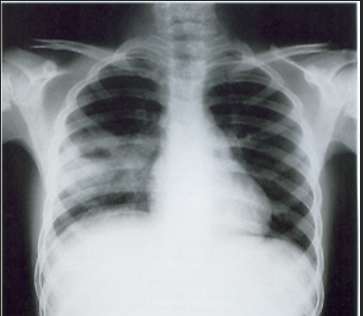

A 3-year-old child is admitted to the hospital due to decreased appetite and weight loss. She has been afebrile, and has not had vomiting or diarrhea.

Her activity level has decreased over the past two weeks.

She had been healthy until 2 months ago, when she was hospitalized for 48 ...

infection with mild respiratory distress and poor fluid intake.